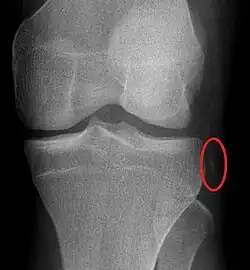

Segond fracture of left knee

The Segond fracture is a type of avulsion fracture (soft tissue structures pulling off fragments of their bony attachment) from the lateral tibial plateau of the knee, immediately below the articular surface of the tibia (see photo).

Segond and reverse Segond fractures are characterized by a small avulsion,[5] or "chip", fragment of characteristic size that is best seen on plain radiography in the anterior-posterior plane. The avulsed fragment of bone may be very difficult to see on the plain x-ray exam, and may be better seen on computed tomography. MRI may be useful for visualization of the associated bone marrow edema of the underlying tibial plateau on fat-saturated T2W and STIR images, as well as the associated findings of ligamentous and/or meniscal injury.